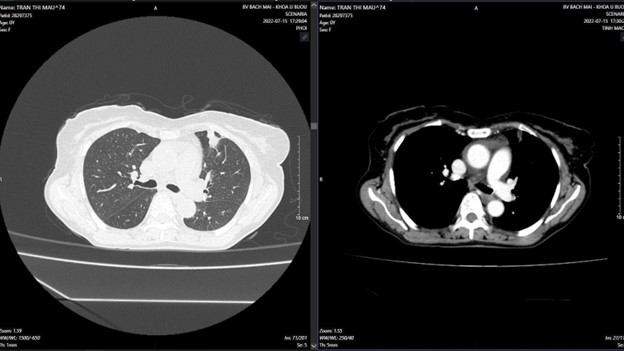

+ Sau điều trị 18 tháng:

Hình 4: Hình ảnh nốt đặc thùy trên phổi trái đường kính 9mm, màng phổi hai bên không thấy dịch-khí